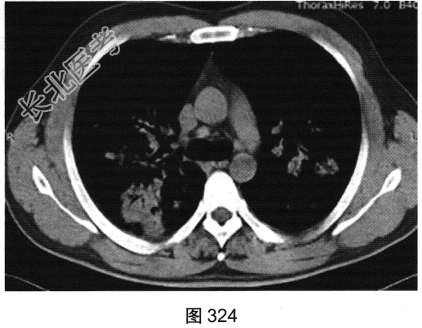

- [材料题] 患者男性,30岁,发作性咳喘3年,吸入冷空气后鼻塞、流黄白色脓涕,外院予环丙沙星治疗后症状缓解,其后鼻塞,夜间睡眠中喘憋反复发作;咯血、发热1周,以傍晚和夜间为著,体温最高为38.5℃,伴畏寒及周身疼痛,痰中带血,为鲜红色,伴胸痛、咳嗽,喘憋明显。胸部CT检查如图319~图324所示。

- 多项选择题4.下列哪些疾病可以出现反晕征( )

A、机化性肺炎

B、非特异性间质性肺炎

C、肺结核

D、肺栓塞

E、结节病

F、真菌感染